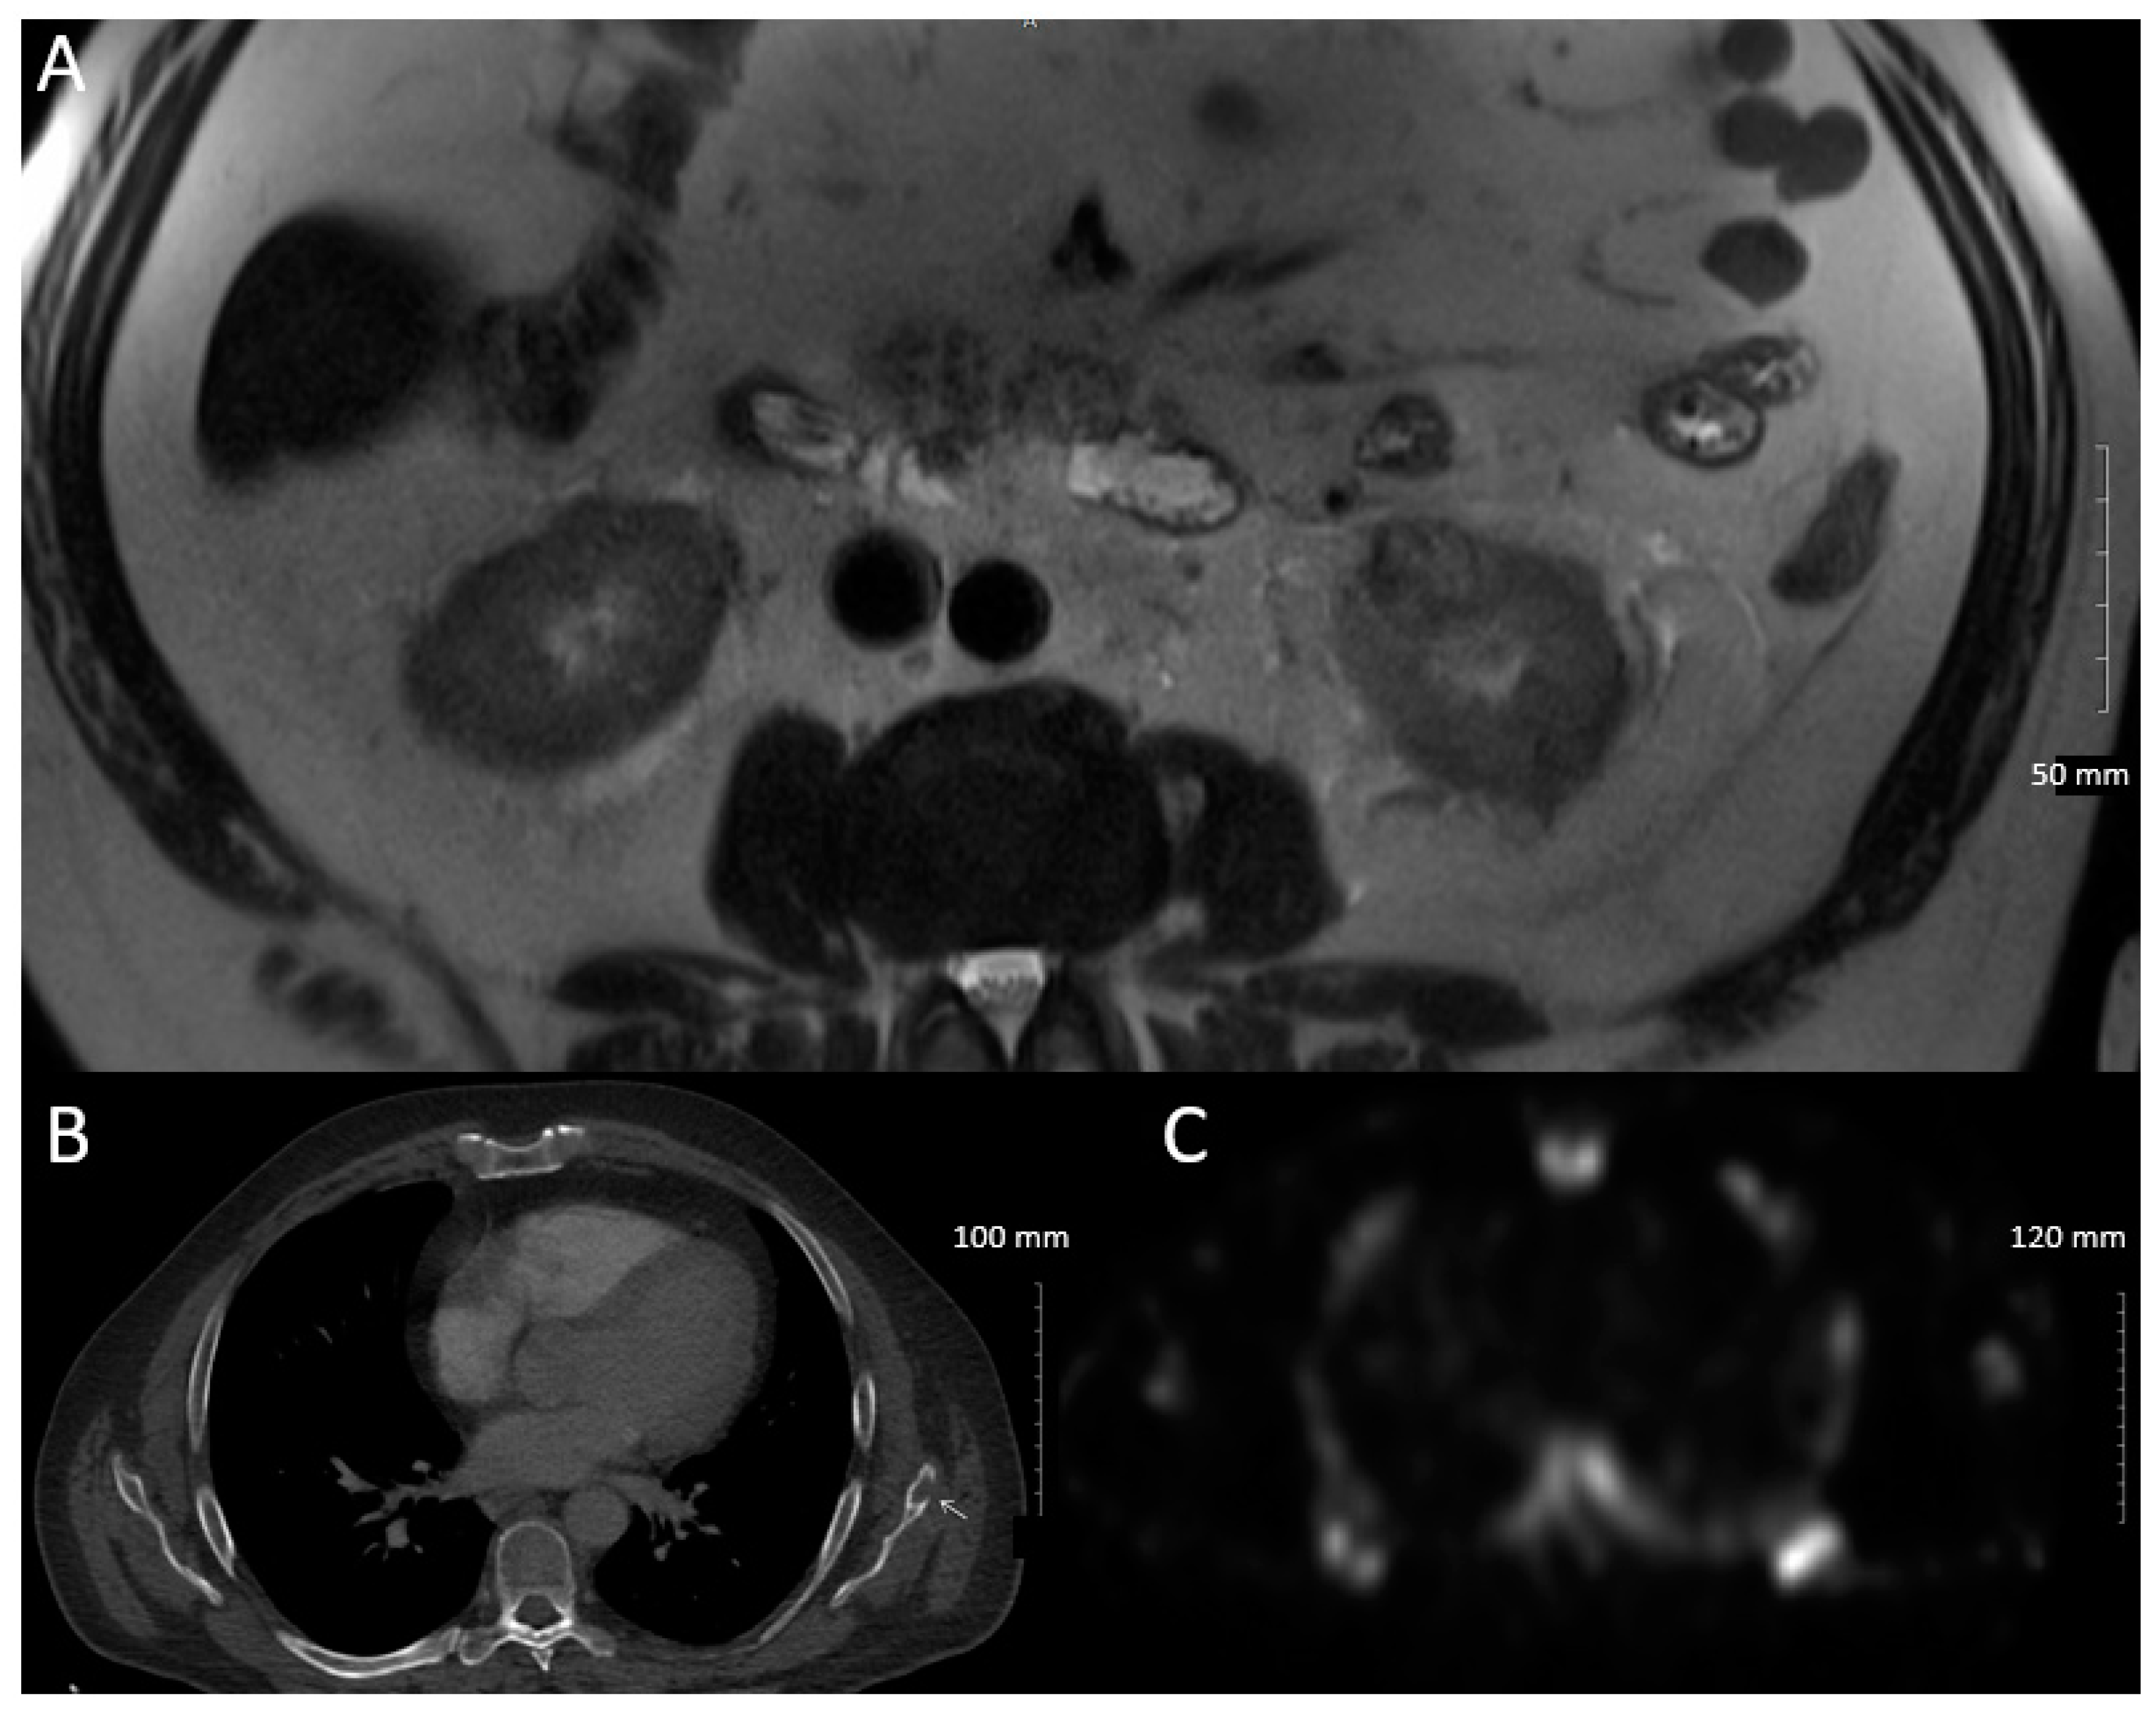

2. Case